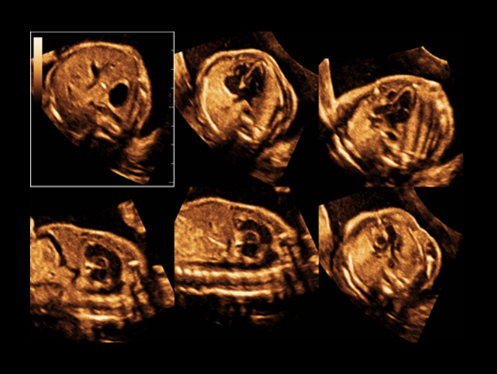

El ecГіgrafo DC-80A con X-Insight proporciona una soluciГіn excepcionalmente inteligente para la completa salud de la mujer, desde fertilidad hasta el cribado prenatal y asistencia sanitaria posparto.